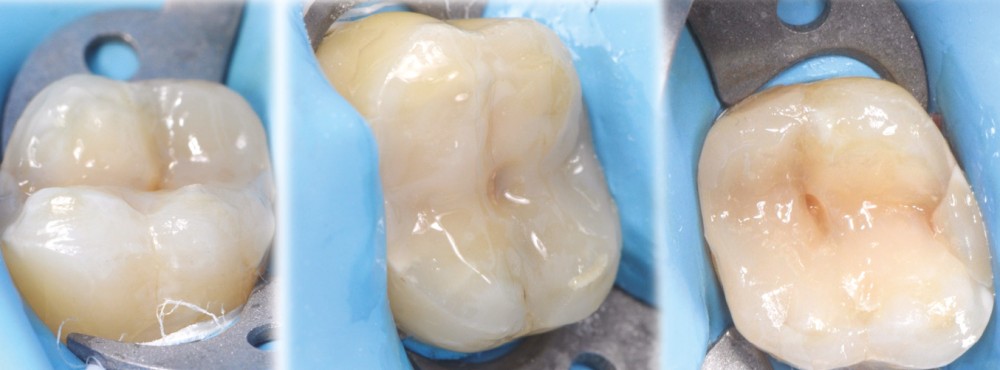

à ces restaurations correspond aujourd’hui toute une série de nouveaux design postérieurs permettant une ultra-préservation tissulaire et pouvant s’inscrire, en fonction des situations cliniques, dans l’émail (situation idéale), dans la dentine, dans le composite de base intermédiaire, ou un « mix » de ces différents supports (fig. 10 à 13).

Les épaisseurs de préparation varient donc selon la nature du support. De 0,6 à 1 mm d’épaisseur sur l’émail jusqu’à 1,5 mm sur la dentine ou le composite afin d’être en adéquation avec les modules d’élasticité des matériaux de restauration utilisés (céramique ou composite).